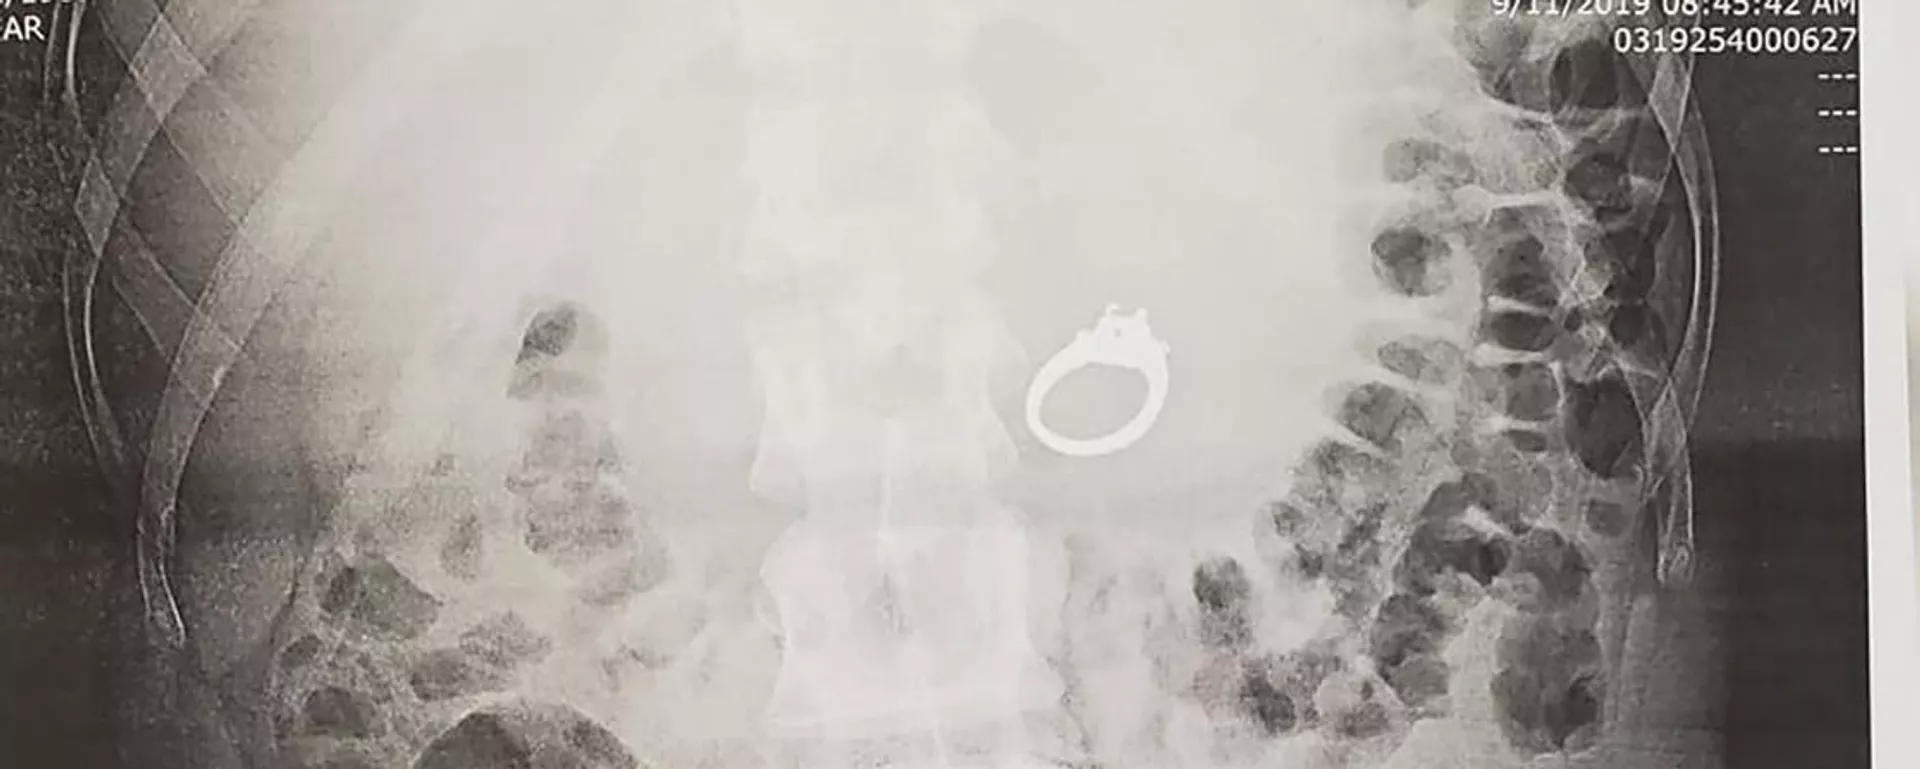

Pranešama, kad egiptietis kreipėsi į gydytojus su skundais dėl pilvo skausmo. Apžiūros metu vyrui buvo padaryta rentgeno nuotrauka, kuri parodė, kad jo skrandyje yra mobilusis telefonas.

Gydytojai pareiškė, kad jie buvo šokiruoti to, ką pamatė. Pacientas prisipažino, kad prietaisą prarijo prieš šešis mėnesius, tačiau jam buvo gėda eiti į kliniką, nors visą laiką kentėjo nuo skausmo.

Jis sakė, kad tikėjosi natūraliai atsikratyti telefono, tačiau to neįvyko. Dėl to vyrui prireikė chirurginės pagalbos jį pašalinti.

Svetimas daiktas trikdė normalų virškinimą, tai ir sukėlė skausmingus pojūčius.